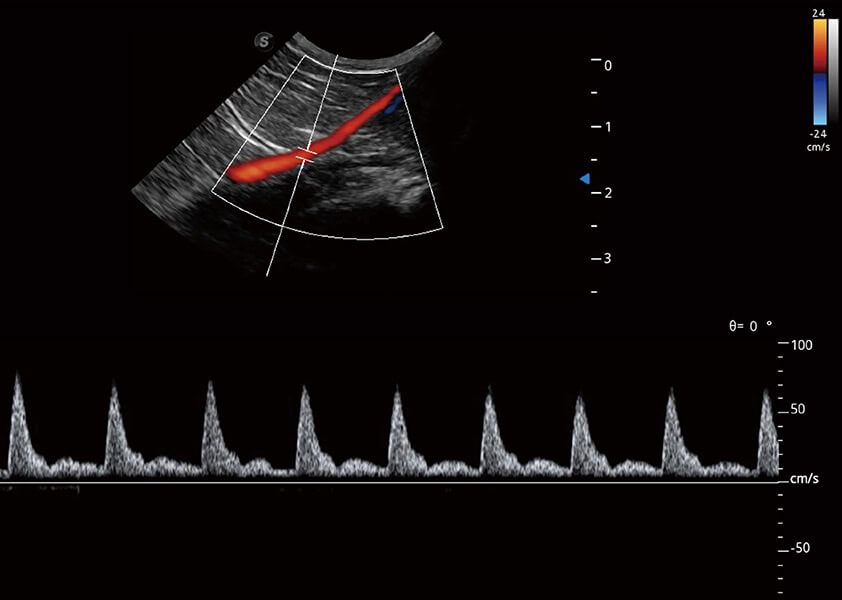

优异的基础图像

(犬)四腔心血流

(猫)髂动脉血流频谱

(犬)肾脏血流